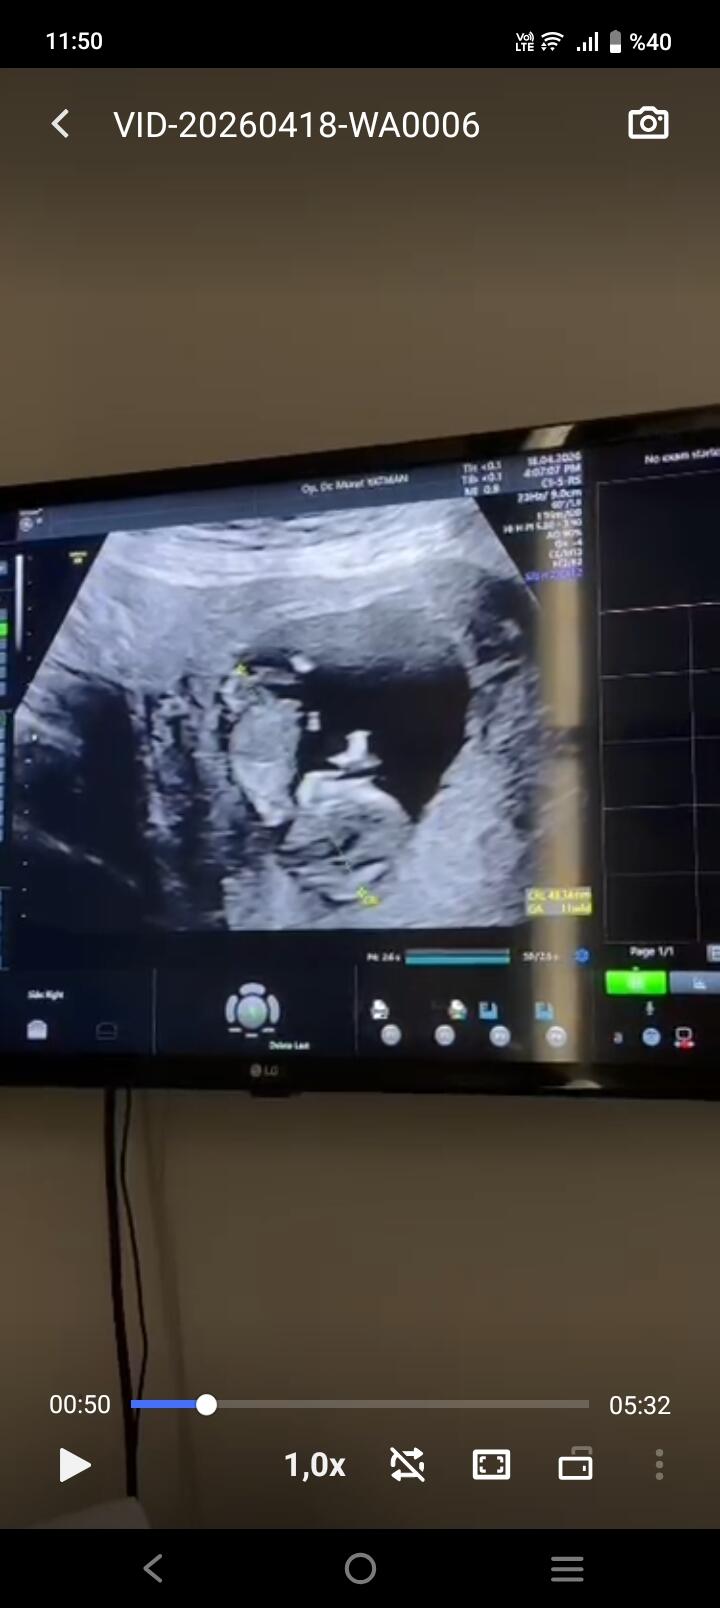

Kese şekline göre kız bebek diyecegim canim

Canım çok net değil ama başka var mı yakin ve net tahmin edecek olursak erkek bebek gibi

Ters duruyor du zaten baş aşağı dı Doktor ne kız dedi ne erkek haftaya konuşuruz dedi kararsız kaldım dedim

Anladım baş aşağı durduğunu orda çıkıntı var o yüzden erkek gibi geldi kordon değil ise

Bence kız mercimek gibi olursa kız derler fasulye gibi olurs erkek derler hakkında hayırlısı olsun canım